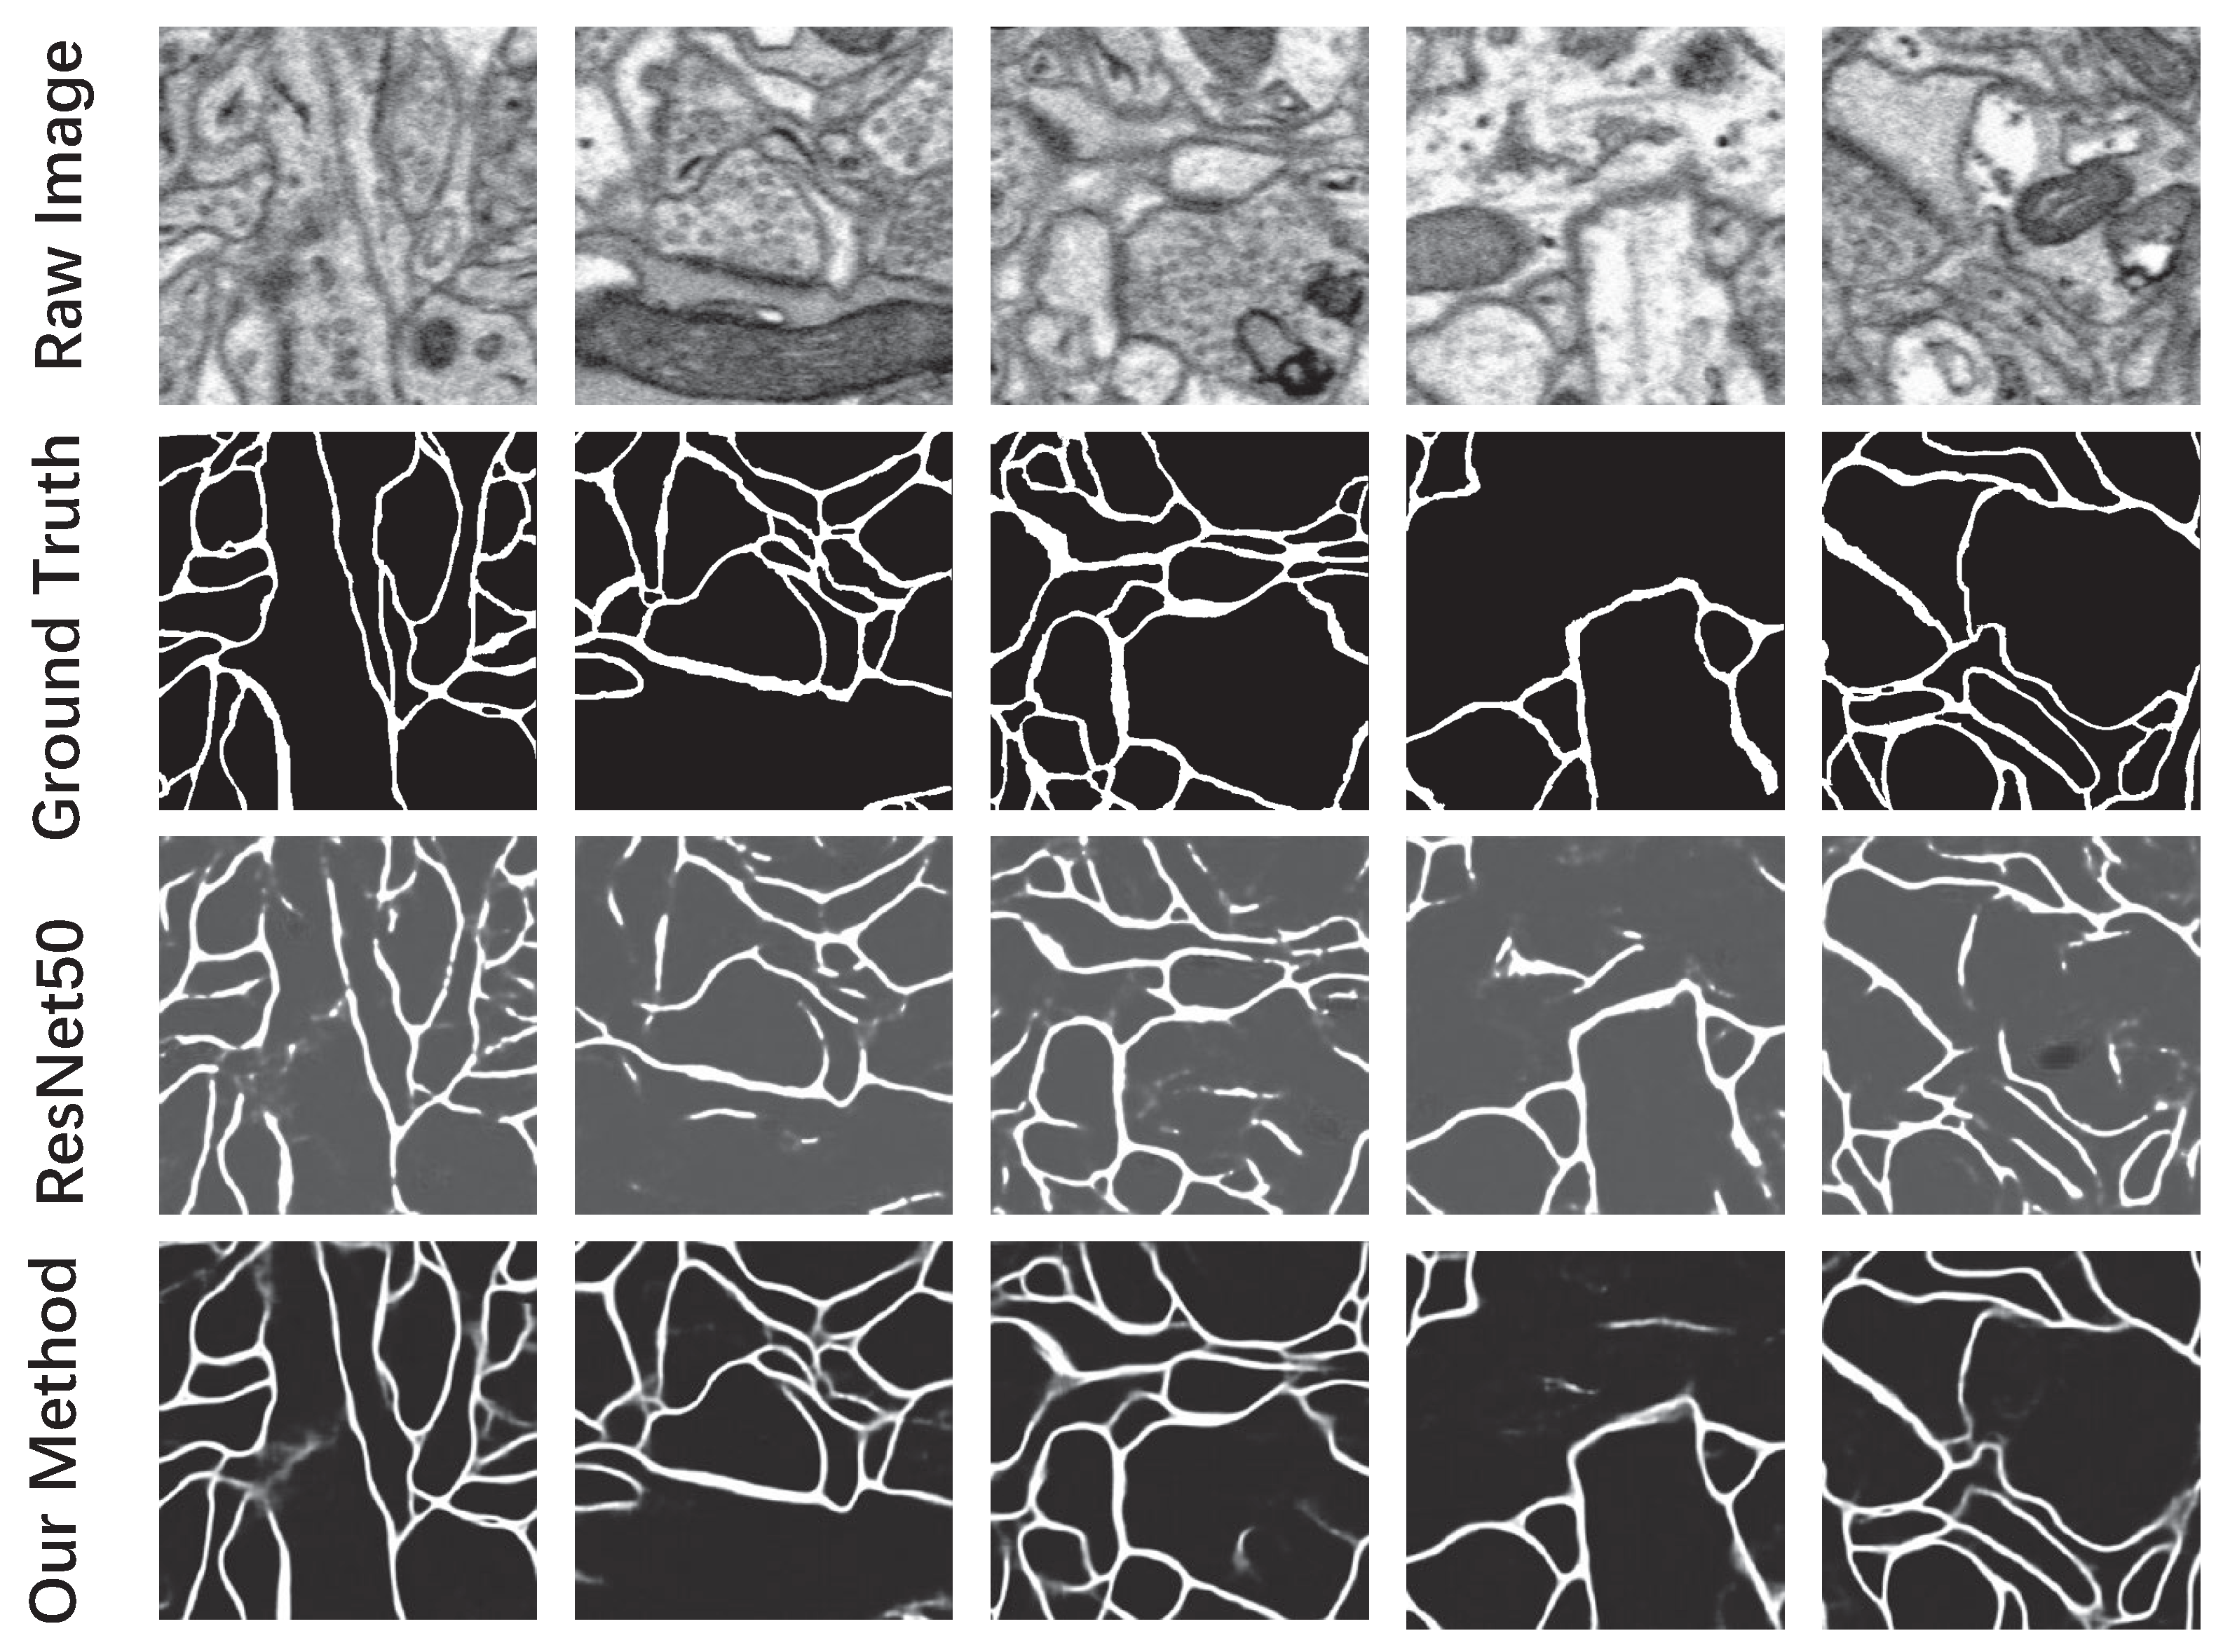

3.3.1. Probability Map of the Neuronal Membrane

| Our Method | ResNet50 [37] | |

|---|---|---|

| Pixel-error | 5.61% | 7.81% |

| Rand-error [32] | 12.74% | 27.34% |